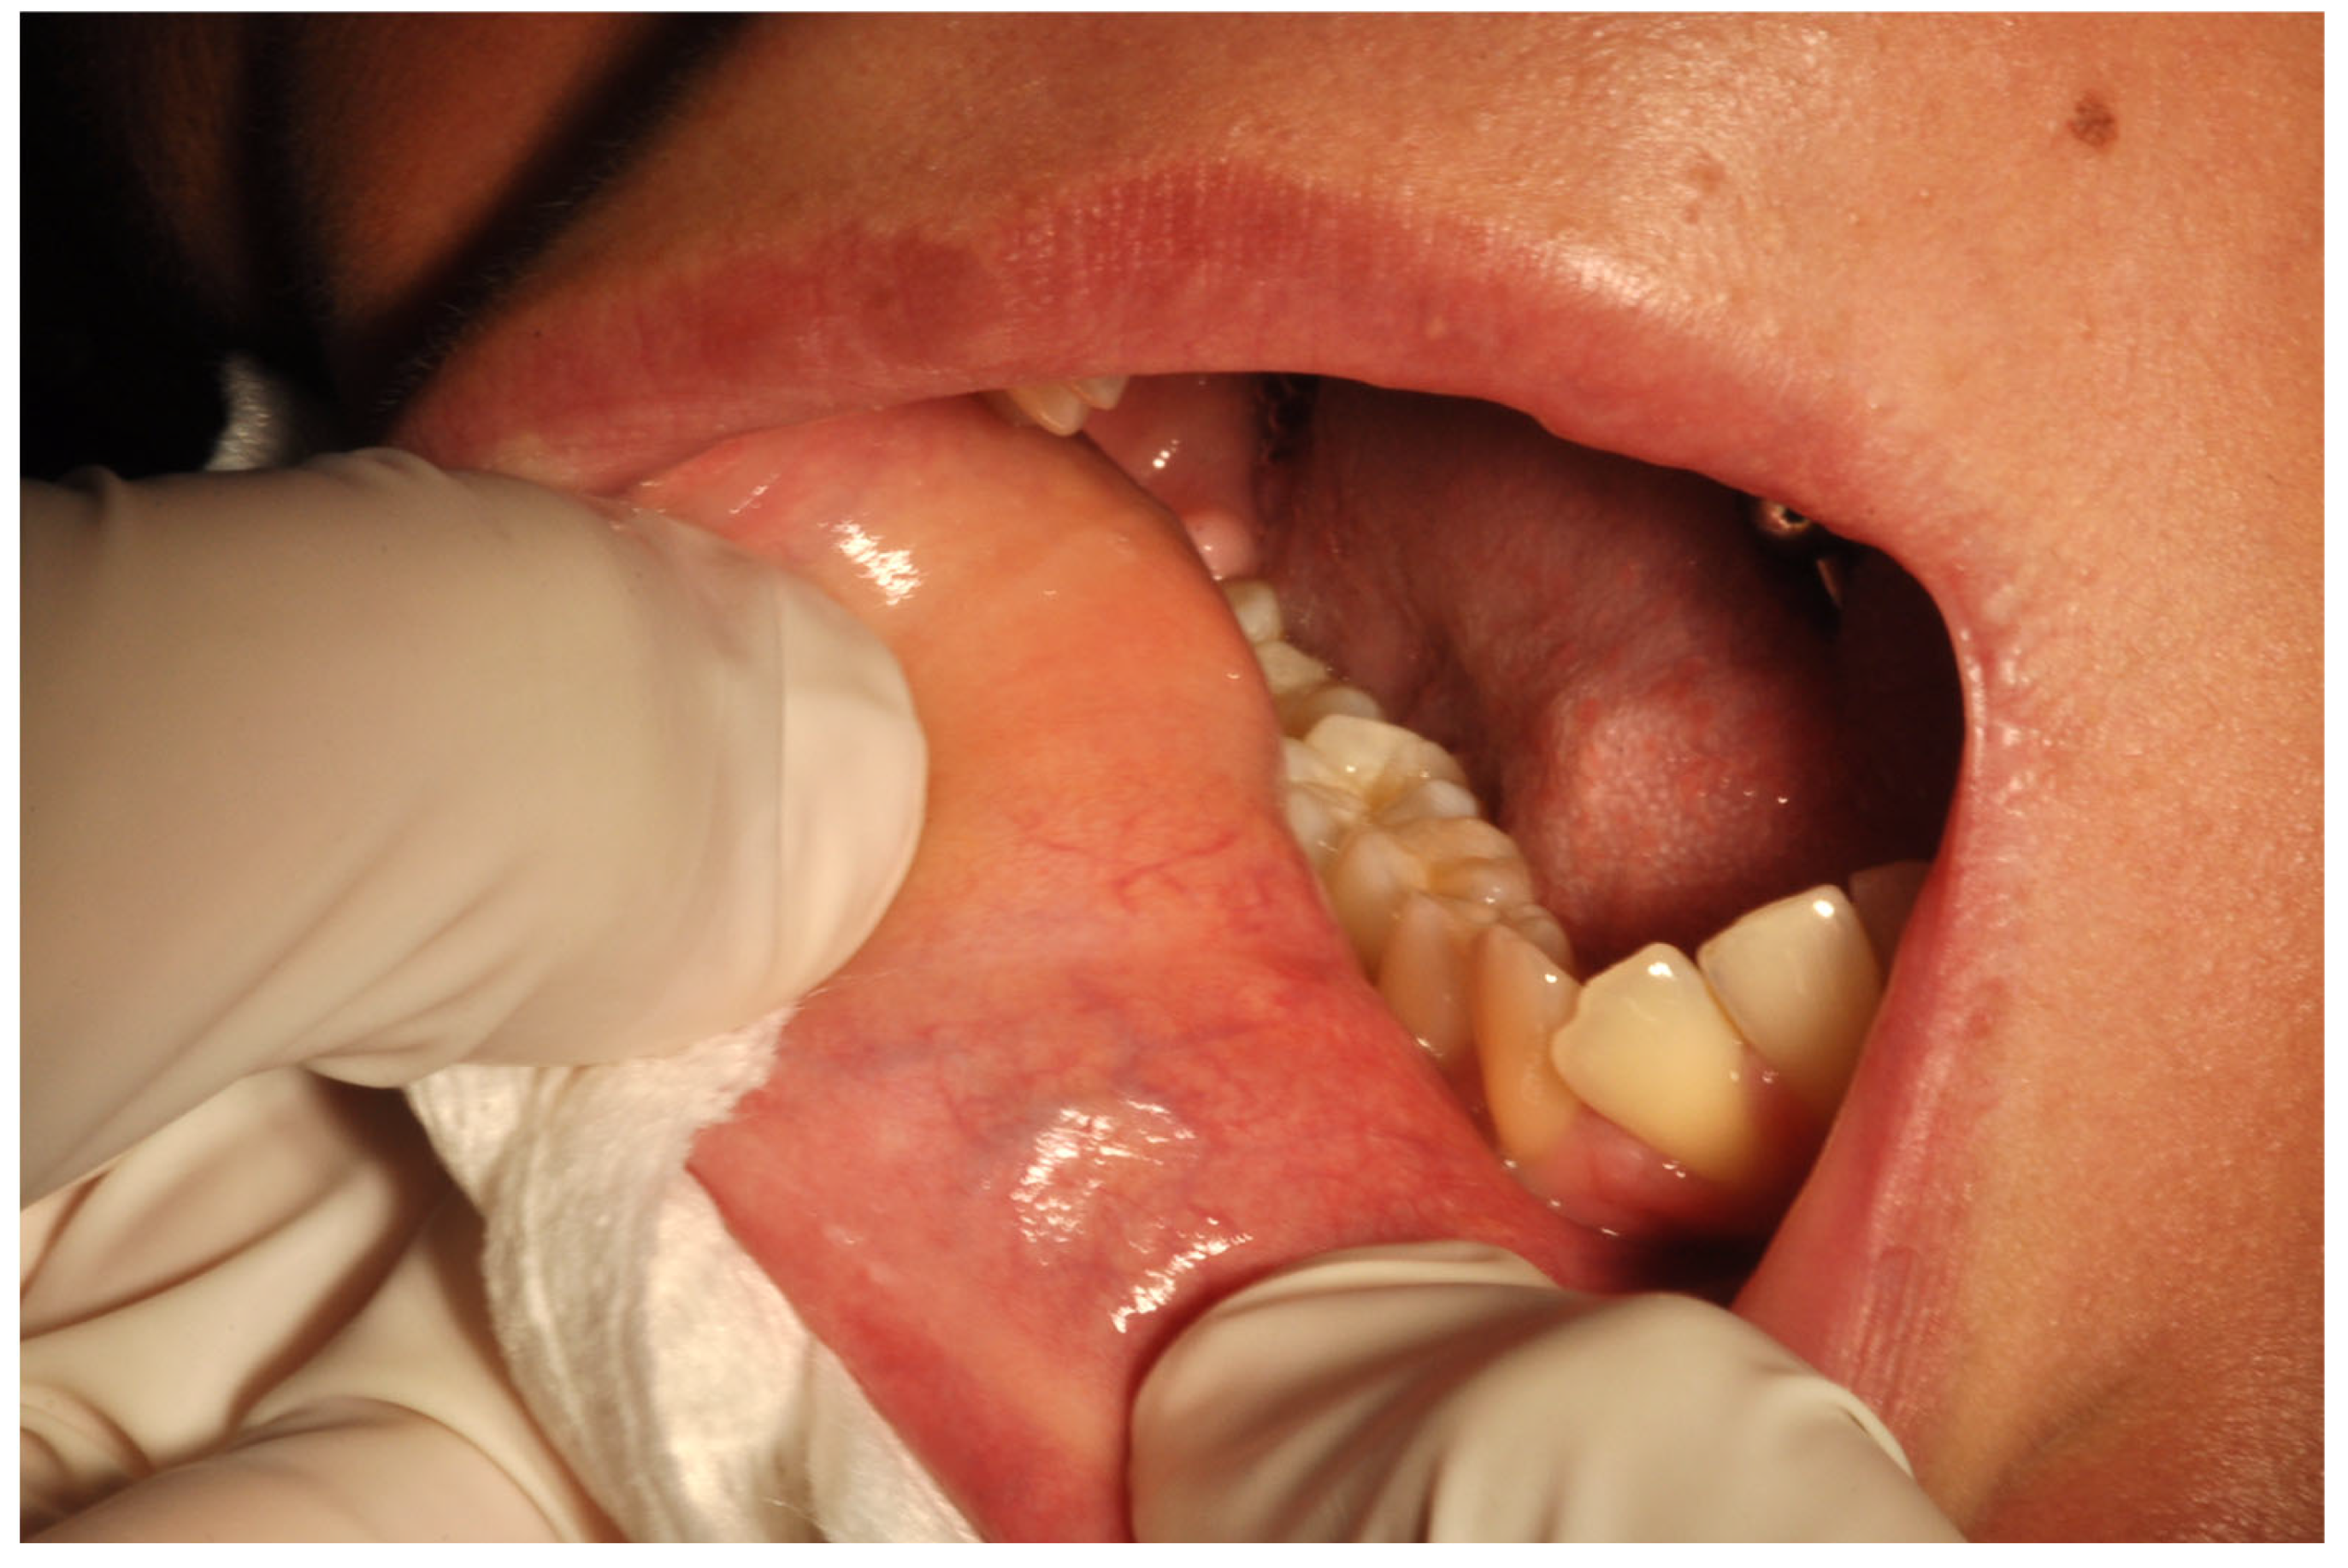

2.1. Case Report

3.1. Histological and Clinical Follow-Up